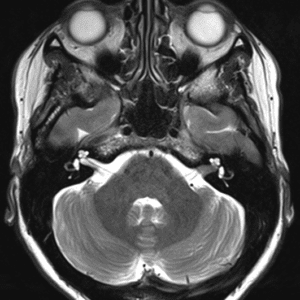

U dây VIII

Lượt xem: 140» 24-11-2018 -

U dây VIII

Lượt xem: 131» 24-11-2018 -

U dây VIII

Lượt xem: 143» 24-11-2018 -

U dây VIII

Lượt xem: 155» 24-11-2018 -

U dây VIII

Lượt xem: 124» 19-11-2018 -

U dây VIII

Lượt xem: 159» 05-11-2018 -

U dây VIII

Lượt xem: 239» 30-10-2018 -